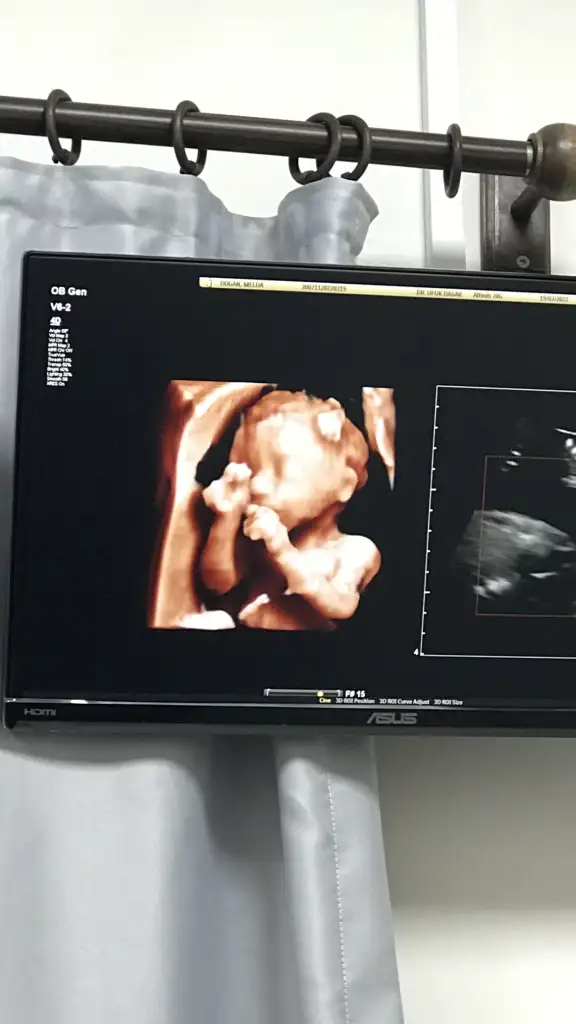

YyaaaaaGelinliğimi bulamadım ama size oğluşumu göstereyimmelek oğlum benim detaylı ultrason anımız

Gelinliğimi bulamadım ama size oğluşumu göstereyimmelek oğlum benim detaylı ultrason anımız

Çok güzelmiş maşallah. Parmağını emiyor sanki sıpaGelinliğimi bulamadım ama size oğluşumu göstereyimmelek oğlum benim detaylı ultrason anımız

Kuzum benimGelinliğimi bulamadım ama size oğluşumu göstereyimmelek oğlum benim detaylı ultrason anımız

Evet banada parmak emiyor gibi geldiÇok güzelmiş maşallah. Parmağını emiyor sanki sıpa